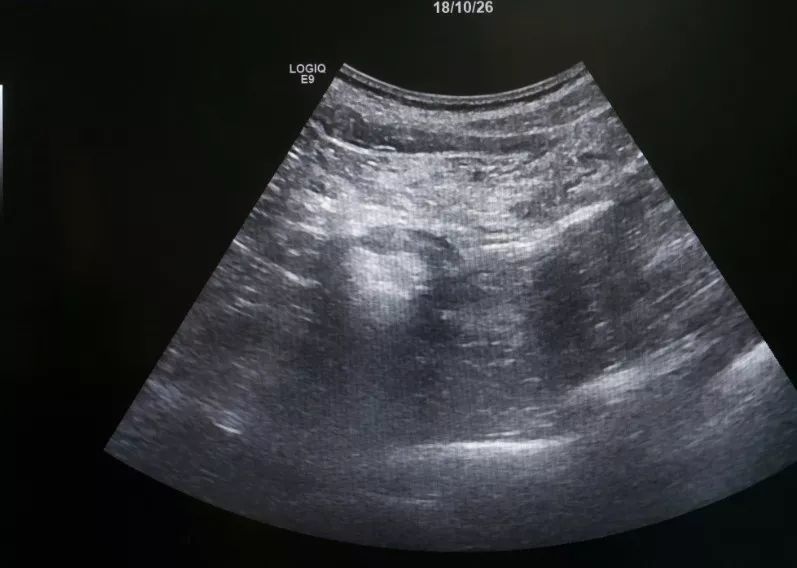

肾肿瘤彩超

肾肿瘤彩超,肾肿瘤ct

请各位同仁看像肾肿瘤吗

肾肿瘤超声诊断_肾癌_医疗健康_医疗健康其他